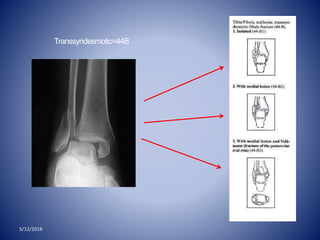

Transsyndesmotic=44B